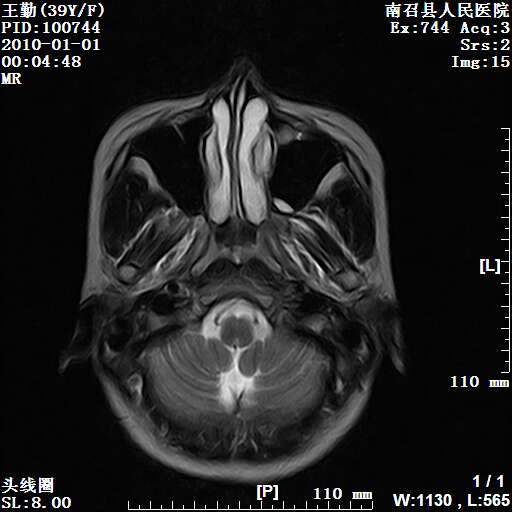

以下是引用随光逐影在2010-1-22 9:03:00的发言:[br]考虑左侧中颅窝(蝶骨翼区)脑膜瘤侵犯蝶骨翼并突入左侧眼眶。

以下是引用水过无痕在2010-1-22 14:55:00的发言:[br]一、定位:颅外占位;二、定性:恶性可能性大;三、组织来源:来源于左侧眼外直肌或其他部位;考虑为:横纹肌肉瘤>转移瘤>脑膜瘤.